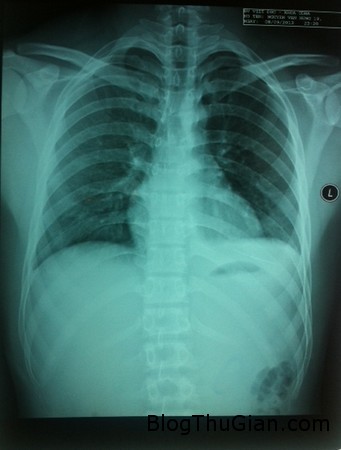

Theo lời kể của người nhà, vào tối 7/9, do sơ suất Văn đã nằm đè lên chiếc kim khâu và bị đâm xuyên vào ngực. Lúc đầu, cậu thấy nhói đau nhưng càng về sau cơn đau lại càng dữ dội, vùng ngực bị sưng nề. Thấy vậy gia đình vội đưa cậu đến Bệnh viện tỉnh khám và sau đó bác sĩ đã chuyển cậu tiếp lên Bệnh viện Việt Đức (Hà Nội). Tại đây sau khi hội chẩn các bác sĩ quyết định mổ tim hở khẩn cấp để cứu bệnh nhân.

Cây kim đâm xuyên qua ngực đâm vào tim bệnh nhân. Ảnh: Bệnh viện cung cấp.

Theo điều dưỡng trưởng Nguyễn Xuân Vinh, khoa Tim mạch lồng ngực, bệnh nhân vào viện chỉ với biểu hiện đau ngực nhiều, vết thương ở ngực trái rất bé. Tuy nhiên nếu không mở lấy cây kim ra sớm, khi tim co bóp cây kim có thể đâm thủng tim bệnh nhân. Nếu nó trôi ra khỏi quả tim vào mạch máu thì sẽ rất nguy hiểm vì không biết đường nào mà tìm.

Sau 2 giờ phẫu thuật, các bác sĩ đã lấy ra được cây kim dài 4,5 cm. Phó giáo sư Nguyễn Hữu Ước, Trưởng khoa Tim mạch Lồng ngực cho biết, đây là trường hợp rất hy hữu, lần đầu tiên gặp tại Bệnh viện Việt Đức. Khi mở vùng tim ra, tim của bệnh nhân đã rách nham nhở.